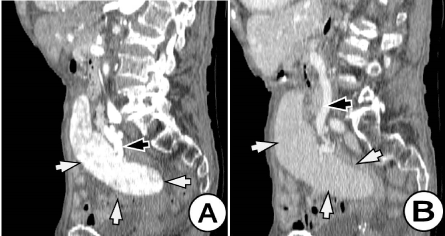

Here in, we present a case of a patient with a pelvic spleen causing discreet abdominal pain or abdominal discomfort. A 67 years old woman was admitted to the surgical department complaining of discreet abdominal pain and lower abdominal tenderness. Physical examination revealed abdominal distention, predominantly in the lower abdomen due to a tender mass. The diagnosis of abdominal wall herniation was suspicions and the patient was undergone to CT investigation of the abdomen. A Computed tomography performed for abdominal wall herniation revealed a pelvic solid formation, well vascularized, approximately 12 cm in length, occupying the pelvis, with a long pedicle of tortuous vessels and with features of an ectopic spleen. (Figures 1 and 2) Axial computed tomography (CT) revealed the absence of the spleen in its normal anatomical position (Figure 3) and a homogeneous pelvic mass with contrast enhancement, suggestive of a ectopic spleen (Figure 4). A contrast-enhanced CT image showed the normal spleen, measuring 12×7 cm, suspended by elongated, dilated, and tortuous splenic vessels (Figures 1,2,5). Imaging findings of the ectopic spleen are the absence of the spleen in its normal position and a mass located anywhere in the abdomen or pelvis with enhancement pattern of a normal splenic tissue (Figure 5). The absence of the spleen in its normal position and the enhancement of the pelvic mass made the diagnosis of an ectopic spleen undeniable. Thorough investigation revealed no evidence of accessory spleens in the left upper quadrant,

Figure 1. Corona l(A) and 1(B) reformatted CT scan images of the abdomen post IV contrast administration (arterial phase) showing an ectopic spleen (white arrow) in the left pelvic region extending anterior and lateral to the uterus. The spleen shows normal perfusion. A long tortuous vascular pedicle containing the splenic vessels (black arrow) is seen extending from the epigastric region to the prolapsed spleen. There was a long splenic pedicle containing tortuous vessels with the splenic vein and artery (black arrow)

Figure 2. Sagittal (A) and (B) reformatted CT scan images of the abdomen post IV contrast administration (arterial phase -A) and (venous phase - B) showing an ectopic spleen (white arrow) in the pelvis extending anterior and lateral to the uterus into the left. The spleen shows normal perfusion. A long tortuous vascular pedicle containing the splenic vessels (white arrow) is seen extending from the epigastric region to the prolapsed spleen. There was a long splenic pedicle containing tortuous vessels with the splenic vein and artery. Sagittal contrast enhanced CT image showing a large ectopic spleen in the pelvis suspended by an elongated and tortuous vascular pedicle